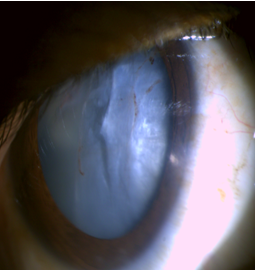

Once it is confirmed a as case of traumatic cataract then it should be determined whether it is secondary to penetrating or blunt trauma. Blunt injury is one which is caused by blunt object like (cricket ball, champagne cork etc.)([Figure 2], [Figure 3]) and penetrating trauma is one which has entry wound but not exit wound, caused by object like (iron rod, wooden stick thorn etc.) ([Figure 4], [Figure 5]) After the mode of injury IOP should be determined if low it always raise the suspicion of open globe injury; however in some cases the wound is self-sealing and IOP may be normal which is confirmed by Siedel’s test which is done at the site of wound first penetrating trauma should be ruled out once it is done the status of posterior segment is seen by ultrasound biomicroscopy. If penetrating trauma is present use of topical medication or instruments that coming in contact with intraocular tissue should be avoided as it interferes with integrity of globe. Patients who were cooperative and willing for the surgery were included after taking the consen.

In our study we found that corneal involvement was most common associated ocular damage ([Figure 6], [Figure 7]) and it was found that it is one the most common cause of reduced visual acuity following penetrating trauma.

Associated ocular injuries (Fig. 1-4)

Before and after surgery (Fig. 5-8)

Our study concludes that the younger males common sufferer than female due their more involvement in outdoor activities. Penetrating injuries being more frequent than the blunt injury. Blunt injury has better visual outcome than penetrating injury because structural integrity is maintained. In case Penetrating trauma BCVA is less due to associated ocular injury, more of corneal involvement. It also depend various factor ranging from force of trauma affecting anterior and posterior segment ([Figure 6], [Figure 8]), severity of damage, any preceding ocular conditions, proper and timely medical and surgical management of these cases, and management of post operative complications and regular followup.